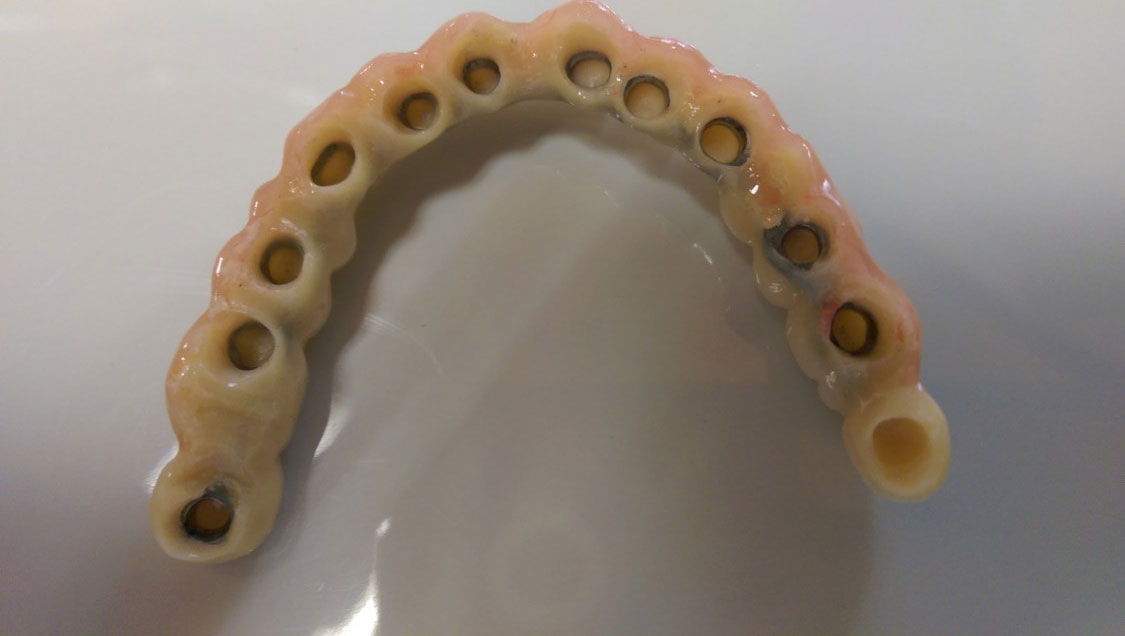

• esettanulmany-08

Műtét másnapján, implantátumok a szájban.

• esettanulmany-09

Így néz ki a hosszútávú ideiglenes híd.(Fém vázzal erősített műanyag híd.)

• esettanulmany-40

• esettanulmany-41

Így néz ki a hosszútávú ideiglenes híd. (Fém vázzal erősített műanyag híd.)

• esettanulmany-42